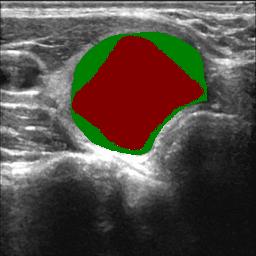

3.4.3 Prototype Correlation Loss for Boundary-level Shape Learning

To learn pixel-wisely precise segmentation shapes, building on the segmentation objective defined as Eq. (3), we extend the shape constraint to boundary-level by introducing a prototype correlation loss, to make the uncertain pixels on the classification boundary in the feature space closer to their category prototypes.

As illustrated in Fig. 4, given the high-confidence foreground and background labels and , we first extract the corresponding region features and . The foreground/background prototype and is obtained by extracting deep features located in regions of the high-confidence foreground/background labels and performing average pooling, where means feature channels.

| (10) | ||||

This loss comprises two components: 1) complementary consistency between feature correlations that refer to high-confidence foreground prototype and background prototype, and 2) consistency between network segmentation results and fused correlation segmentation results.

Using metric learning, we evaluate the correlation response of each position in the feature map with respect to the foreground prototypes and background prototypes, obtaining the foreground correlation response and the background correlation response as follows:

| (11) | |||

Since foreground and background are mutually exclusive in segmentation tasks, the foreground correlation response can be derived from the background prototype as follows:

| (12) |

The correlation map represents the similarity between image features and each prototype. The first component of the prototype correlation loss reflects the complementary consistency between the feature correlations referring to high-confidence foreground and background prototypes, which is defined as follows:

| (13) |

The fused predictions are obtained by balancing the foreground correlation maps based on the foreground and those on the background prototypes.

| (14) |

The second component of the correlation loss that measures the consistency between the fused correlation map and the segmentation prediction is defined as:

| (15) |

The total prototype correlation loss is then calculated as follows:

| (16) |

By considering the complementary consistency of foreground and background prototype correlation, the algorithm obtained segmentation edges with low uncertainty. By directly propagating the fused segmentation boundaries to the predicted results, we achieve explicit shape learning, effectively addressing the challenge of refining the boundaries of nodule regions.